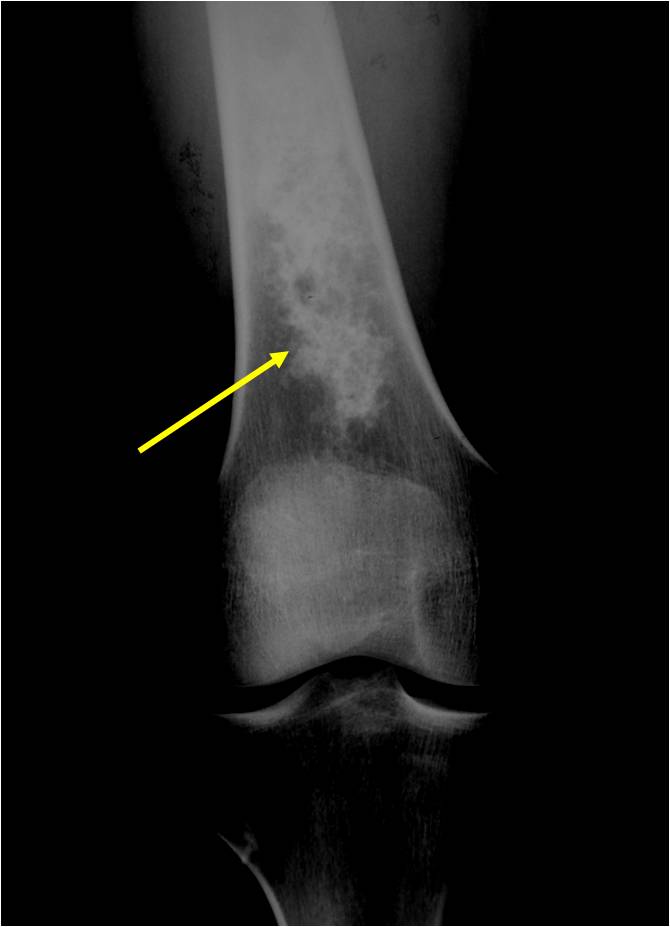

- Localized, radiolucent defect usually with punctate calcifications

- Calcifications are typical but not always present

- Matrix may demonstrate various degrees of calcification

- Calcifications are stippled, punctate, popcorn like calcifications and “Ring and Arc” calcifications

- Cartilage tumors grow in a lobular manner. The perimeters of the lobules undergo

- enchondral ossification that may calcify. If the entire perimeter of the lobule calcifies it appears

- radiographically as a “Ring”. If a portion of the perimeter of a lobule calcifies it forms an “Arc” on

- an X-ray.

- Most commonly found in metaphysis

Plain X-Ray:

- Geographic lytic lesion

- Central often metaphyseal in long bones

- Can be eccentric also

- Expansile remodeling with thinned cortex

- Chondroid matrix with calcifications in majority of tumors

- Approximately 20% have limited or no calcifications